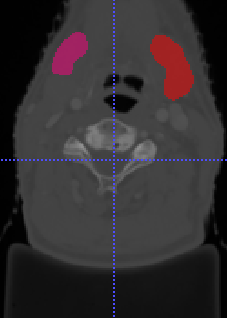

In Chapter 6, we propose an end-to-end, atlas-free 3D convolutional deep learning framework for fast and fully automated whole-volume HaN anatomy segmentation [115]. Our deep learning model, called AnatomyNet, segments OARs from head and neck CT images in an end-to-end fashion, receiving whole-volume HaN CT images as input and generating masks of all OARs of interest in one shot. AnatomyNet is built upon the popular 3D U-net architecture, but extends it in three important ways: 1) a new encoding scheme to allow auto-segmentation on whole-volume CT images instead of local patches or subsets of slices, 2) incorporating 3D squeeze-and-excitation residual blocks in encoding layers for better feature representation, and 3) a new loss function combining Dice scores and focal loss to facilitate the training of the neural model. These features are designed to address two main challenges in deep-learning-based HaN segmentation: a) segmenting small anatomies (i.e., optic chiasm and optic nerves) occupying only a few slices, and b) training with inconsistent data annotations with missing ground truth for some anatomical structures. We collect 261 HaN CT images to train AnatomyNet, and use MICCAI Head and Neck Auto Segmentation Challenge 2015 as a benchmark dataset to evaluate the performance of AnatomyNet. The objective is to segment nine anatomies: brain stem, chiasm, mandible, optic nerve left, optic nerve right, parotid gland left, parotid gland right, submandibular gland left, and submandibular gland right. Compared to previous state-of-the-art results from the MICCAI 2015 competition, AnatomyNet increases Dice similarity coefficient by 3.3% on average. AnatomyNet takes about 0.12 seconds to fully segment a head and neck CT image of dimension , significantly faster than previous methods. In addition, the model is able to process whole-volume CT images and delineate all OARs in one pass, requiring little pre- or post-processing. We demonstrate that our proposed model can improve segmentation accuracy and simplify the auto-segmentation pipeline. These contributions are released as an open-source software package called AnatomyNet, which is publicly available555https://github.com/wentaozhu/AnatomyNet-for-anatomical-segmentation. Portions of this chapter were published as part of [115].